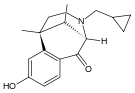

There are a number of broad classes of opioids:[260]

- Esters of morphine opiates: slightly chemically altered but more natural than the semi-synthetics, as most are morphine prodrugs, diacetylmorphine (morphine diacetate; heroin), nicomorphine (morphine dinicotinate), dipropanoylmorphine (morphine dipropionate), desomorphine, acetylpropionylmorphine, dibenzoylmorphine, diacetyldihydromorphine;[261][262]

- Semi-synthetic opioids: created from either the natural opiates or morphine esters, such as hydromorphone, hydrocodone, oxycodone, oxymorphone, ethylmorphine and buprenorphine;

Benzomorphan derivatives

- Dezocine—agonist/antagonist

- Pentazocine—agonist/antagonist

- Phenazocine

Oripavine derivatives

- Buprenorphine—partial agonist

- Dihydroetorphine

- Etorphine